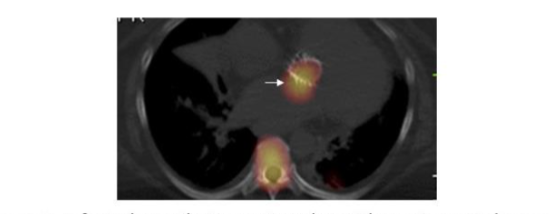

Labeled leukocyte imaging also is useful in cardiovascular infections. This test is a useful adjunct in patients with suspected infective endocarditis, especially those involving prosthetic valves (Figure 7)¹⁷,¹⁸. In one investigation WBC SPECT/CT was 90% sensitive and 100% specific for infective endocarditis and was particularly useful in patients who were classified as possible infective endocarditis by the Dukes Criteria¹⁷.

Figure 7.

Infected prosthetic aortic valve with aortic root abscess. Axial SPECT/CT demonstrates intense uptake of indium-111 labeled leukocytes around the valve extending into the aortic root (arrow). Transesophageal echocardiogram performed 5 days earlier was negative.